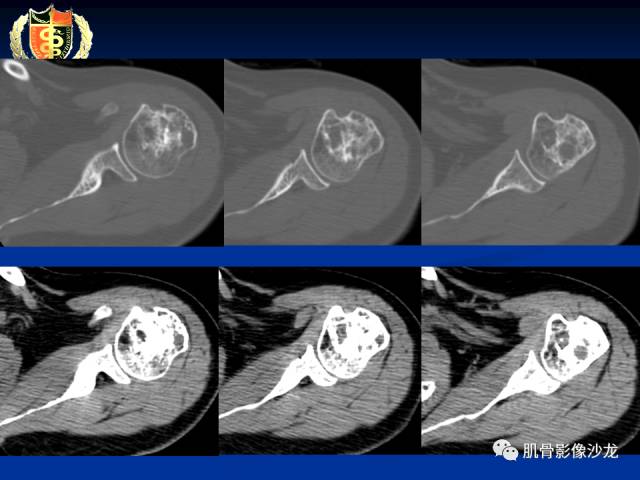

骨淋巴瘤及软骨肉瘤两例CT及MR影像表现

内生软骨瘤?

有症状,有骨膜反应,还是考虑肉瘤比较合适

软骨肉瘤?

目前看考虑软骨来源是合理的

这些应该是钙化吧

软粘纤的钙化不多见

还是支持软骨肉瘤

不能除外骨肉瘤